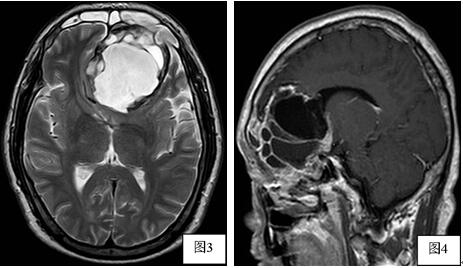

头颅CT(图1)示左前颅窝底一较大占位病灶,大小约7.05cm×5.20cm×7.27cm,边缘见高密度硬化边(图1箭头),其内密度不均。MRI平扫(图2,3)示左前颅窝底病灶呈囊实混合性,中央囊性区较大,呈不均匀长T1长T2信号,周围实性区大部呈长T1短T2信号,增强(图4)病灶周围呈不规则环形强化,病灶内见分隔,病灶向下累及左侧筛窦,向上向后推挤左侧额叶,病灶边界清晰,周围受压脑实质未见明确水肿信号。影像诊断考虑偏良性病变,骨源性肿瘤可能性大。

图1:冠状位CT平扫:肿瘤内部不同分隔内低密度区密度不一致,边缘见高密度硬化边(细箭头)。

图2:T1WI,病灶呈低信号为主;图3:T2WI,病灶呈高信号为主,边缘示环形极低信号影;图4:T1WI矢状位增强:边缘呈不均匀强化,中心未见强化.